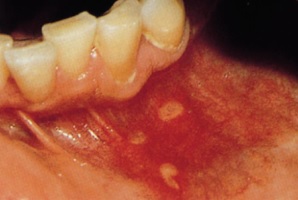

두 번째로 열성 수포라고 불리는 구순 포진은 입술이나 그 부근으로 생기는 수포성 궤양이예요. 구순포진은 헤르페스 바이러스 감염에 의해 생기는 질환입니다. 타인과의 접촉으로 인해 감염되는데있다는데, 경로는 피부 점막을 동원해서라고 해요. 헤르페스 바이러스는 한번 감염되면 평생몸육체에 잠복하고 있다가 그런 순간마다 재발할 수 있습니다.

스트레스, 피로, 발열, 많은 햇빛 노출, 영양 부족, 수면 부족, 감기, 독감 등 면역력이 약해질 때, 생리 등 호르몬 전환가 있을 때에 재발합니다.